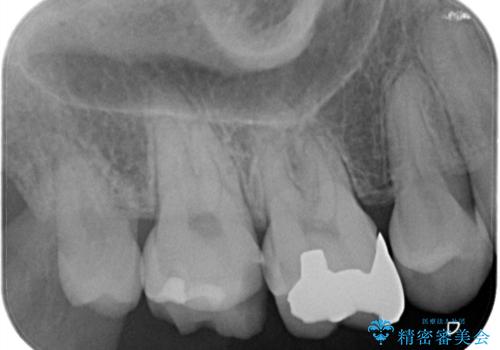

【オールセラミッククラウン】虫歯の治療

- 奥歯がかけたことを主訴に来院されました。

オールセラミッククラウンにて修復治療を行っております。

歯の破折強度を高めるためにクラウンによる修復を希望され、治療を行っております。